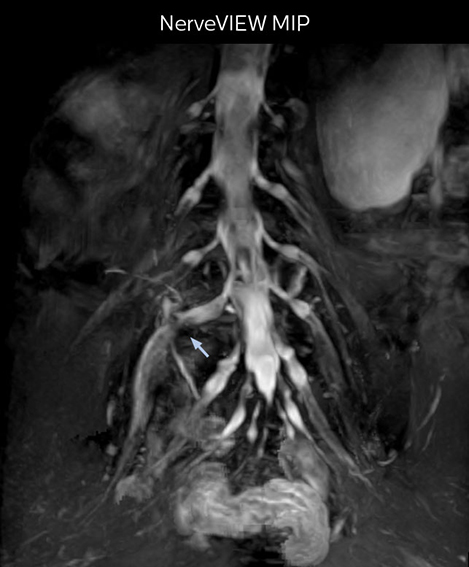

“In patients with lower extremity neurological symptoms, NerveVIEW helps us to determine the disease matching the patient’s symptoms by directly visualizing the nerves. We use the sequence mainly, when there is suspicion of intraforaminal stenosis, extraforaminal stenosis or lateral disc herniation, which is often based on routine T2- and T1-weighted images. Additionally, the excellent depiction of the course of nerves makes NerveVIEW a good navigator when applying treatment such as block therapy or surgery.”

“In such case, we would then browse through axial T2-weighted MR images slice by slice and mentally reconstruct the actual situation based on both radiculography and MRI. Fortunately, NerveVIEW can now very well show nerve courses and presence of nerve compression or edema in one single image series.”

“We have often seen NerveVIEW directly depict details of the nerve compression that were not observed by radiculography. Therefore, we think that with NerveVIEW we can reduce the number of invasive examinations, especially for some patients with lumbar plexus symptoms.”

The key concept in MR neurography, Dr. Yabuki stresses, is the ability to directly visualize spinal nerves, versus inferring the presence of pathology indirectly. “Before NerveVIEW, we estimated compression of the nerve by looking for the presence or absence of fat signal on other MR images,” he says.

“For example, in sagittal images, when the presence of fat is observed in the intervertebral foramen, it suggests that there is a margin around the nerve. Similarly, the absence of fat indicates that the nerve is being compressed. So, we used to deduce nerve compression indirectly. With NerveVIEW, however, we can observe the condition of the nerves directly, regardless of the presence or absence of fat. We always prefer such direct observation of anatomy over having to make an inference about it.”